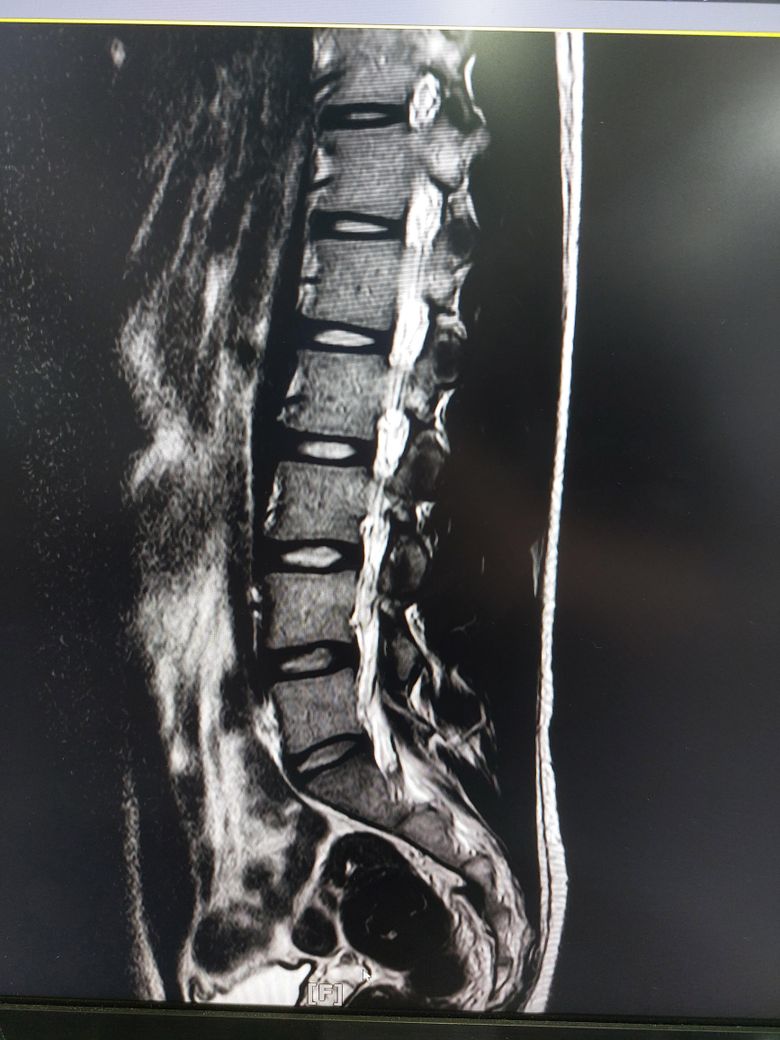

허리디스크 심한편인가요? [Mri 사진 첨부]

멸개월전부터 요추가 뻣뻣하고 시큰거리다가 최근에 좀 나아지긴 해도 만성적이라서 오늘 mri 찍고 허리디스크 진단받았습니다

(요추 맨 밑 천추 위 디스크)

1. 이정도면 아직 팽윤단계인가요?

1. 이정도면 아직 팽윤단계인가요? 디스크 자체도 심하지 않을 뿐더러 그에 따른 증상인지 여부도 확실하지 않습니다